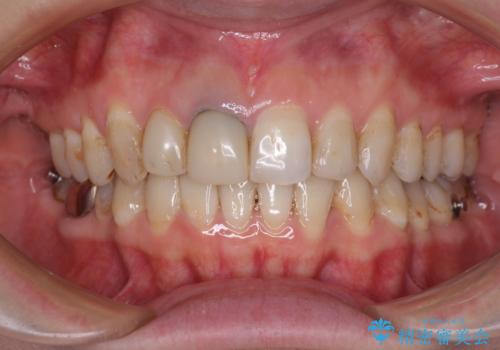

- 前歯の歯並びやむし歯治療の跡、奥歯の銀歯を気にして来院された患者様です。

インビザラインによる矯正治療の後に虫歯や銀歯をセラミックにて補綴することとしました。

前歯のむし歯治療の跡や奥歯の目立つ銀歯がなくなり、明るい口元になりました。